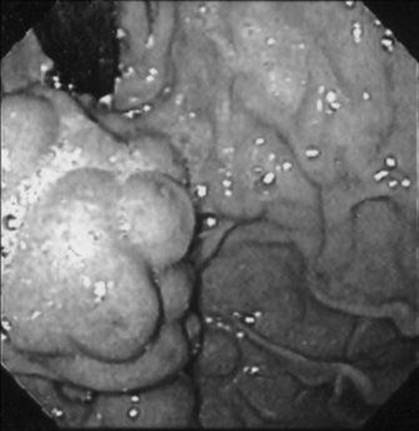

A 35-year-old man presents with massive hematemesis and anemia following an episode of protracted retching. What does the figure show?

Figure 1-2 See also color plate.

Mallory–Weiss tear.